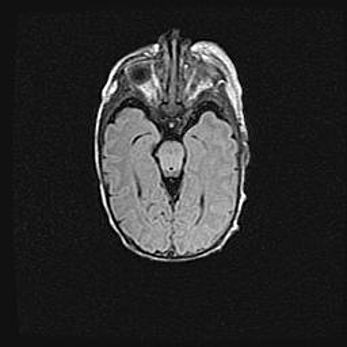

Множественные кисты обоих полушарий головного мозга, наибольшая из них в правой затылочной области. Ассиметричная атрофическая гидроцефалия.

Возраст: 7 месяцев

Вес: 5660 г

Пол: мужской

Окружность головы: 41,5 см

Срок гестации: 28-29 недель

Кисты головного мозга развиваются в результате многоочаговых некрозов вещества мозга и возникают вследствие перенесенной перинатальной инфекции, менингитов, энцефалитов, асфиксии, родовой травмы, расстройств мозгового кровообращения различного генеза. Образованию кист в веществе головного мозга плодов и новорожденных способствуют такие факторы, как высокое содержание в нем воды, недостаточная (или отсутствие) миелинизация и слабая астроглиальная реакция на повреждение.

Кисты могут сочетаться с гидроцефалией и другими поражениями головного мозга.